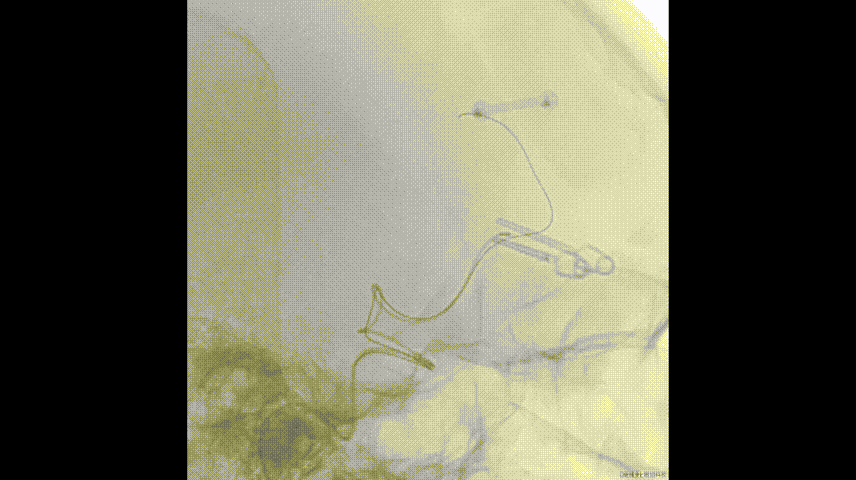

WEB方案

预置微导管

备:上方子瘤填塞、下方子瘤填塞、上干支架

4个月复查,停单抗

发病时头颅CT

国内首例远端侧壁动脉瘤WEB

微导丝支撑和保护下WEB释放、按摩

8个月复查